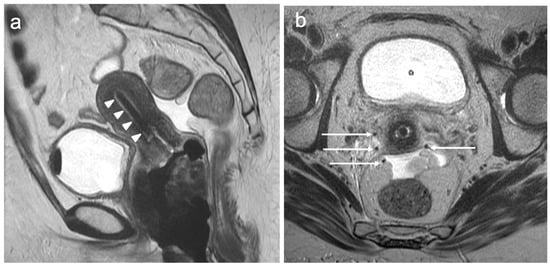

7. FIGO Stage IV

- Pötter, R.; Tanderup, K.; Schmid, M.P.; Jürgenliemk-Schulz, I.; Haie-Meder, C.; Fokdal, L.U.; Sturdza, A.E.; Hoskin, P.; Mahantshetty, U.; Segedin, B.; et al. MRI-guided adaptive brachytherapy in locally advanced cervical cancer (EMBRACE-I): A multicentre prospective cohort study. Lancet Oncol. 2021, 22, 538–547. [Google Scholar] [CrossRef]

- Tanderup, K.; Viswanathan, A.; Kirisits, C.; Frank, S.J. MRI-guided brachytherapy. Semin. Radiat. Oncol. 2014, 24, 181–191. [Google Scholar] [CrossRef]

- Russo, L.; Lancellotta, V.; Miccò, M.; Fionda, B.; Avesani, G.; Rovirosa, A.; Wojcieszek, P.; Scambia, G.; Manfredi, R.; Tagliaferri, L.; et al. Magnetic resonance imaging in cervical cancer interventional radiotherapy (brachytherapy): A pictorial essay focused on radiologist management. J. Contemp. Brachytherapy 2022, 14, 287–298. [Google Scholar] [CrossRef] [PubMed]